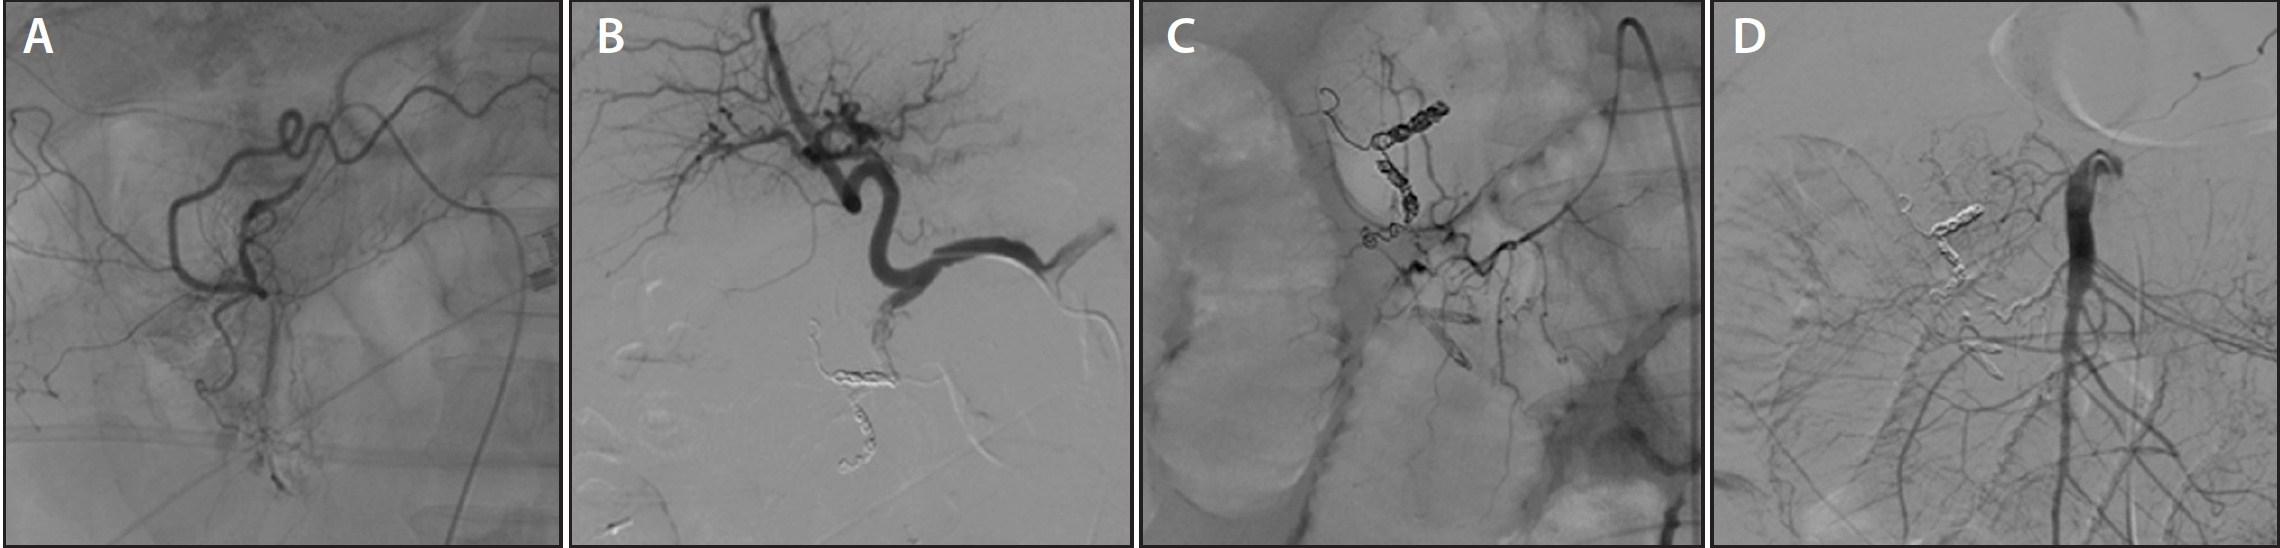

Endovascular Today Embolization for Upper GI Bleeding (April 2016)

Coil Embolization Of Gda The gastroduodenal artery (gda) is frequently embolized in cases of upper gi bleed that has failed endoscopic therapy. Coil embolization in treatment of visceral artery aneurysms and pseudoaneurysms has achieved success rates between 75% and. The gastroduodenal artery (gda) is frequently embolized in cases of upper gi bleed that has failed endoscopic therapy. The purpose of this study was compare embolization of the gastroduodenal artery (gda) using standard pushable coils with the interlock detachable coil. Additionally, it may be done for gda pseudoaneurysms or as an. The best coil position within the gda is as close to the main hepatic artery as possible to exclude perfusion of small pancreaticoduodenal side. We report successful coil embolization of a ruptured gda pseudoaneurysm in a patient with massive gi. Gastroduodenal artery (gda) pseudoaneurysms are among the rarest forms of vapa (<2%). The gastroduodenal artery (gda) is frequently embolized in cases of upper gi bleed that has failed endoscopic therapy.